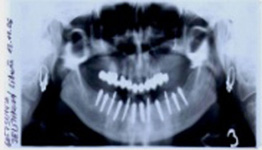

Zavedení implantátů do kosti je většinou ambulantní chirurgický výkon, srovnatelný s vytržením zubu a většinou se provádí v lokální anestézii. Ve výjimečných případech je možné použít i analgosedaci či celkovou narkózu. Operaci provádí zubní lékař-implantolog při dodržení všech podmínek sterility pro operaci. Nástroje pro tuto operaci jsou konstruovány tak, aby výkon byl šetrný vůči kosti a zavedení implantátu bylo provedeno ve velmi krátké době. Díky kvalitní anestézii je výkon nebolestivý. Aby byl pooperační otok co nejmenší, je potřeba operovanou oblast chladit, dle poučení ošetřujícího lékaře. Lékař také ordinuje podle potřeby léky na bolest, případně antibiotika.

Průměrná doba hojení implantátů před provedením definitivního protetického ošetření je 3-4 měsíce, v případech, kde je nutné doplnit chybějící kost (různé metody, postupy a materiály) – tzv. augmentace) se může doba hojení prodloužit na 8-12 měsíců. S tím je pacient vždy předem seznámen svým lékařem.